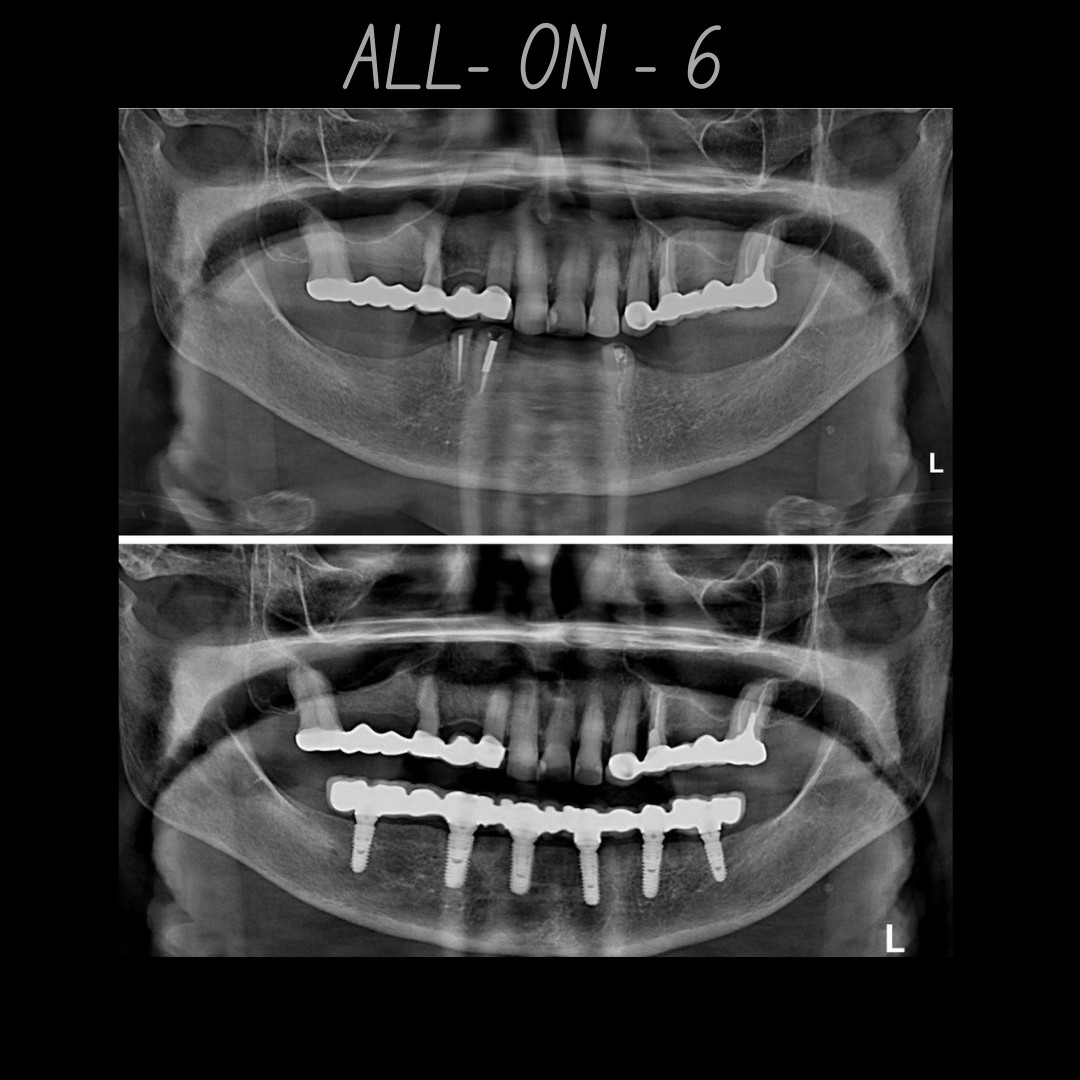

| All-on-6 (per arch) | ₹2,00,000 – ₹4,50,000 |